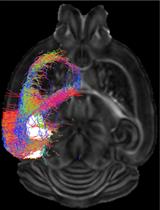

利用弥散磁共振成像绘制小鼠大脑的宏观结构和连接组图

Macroscopic Structural and Connectome Mapping of the Mouse Brain Using Diffusion Magnetic Resonance Imaging

TA Tanzil Mahmud Arefin

CL Choong Heon Lee

JW Jordon D. White

JZ Jiangyang Zhang

AK Arie Kaffman

4671 Views

Nov 20, 2021

Translational work in rodents elucidates basic mechanisms that drive complex behaviors relevant to psychiatric and neurological conditions. Nonetheless, numerous promising studies in rodents later fail in clinical trials, highlighting the need for improving the translational utility of preclinical studies in rodents. Imaging of small rodents provides an important strategy to address this challenge, as it enables a whole-brain unbiased search for structural and dynamic changes that can be directly compared to human imaging. The functional significance of structural changes identified using imaging can then be further investigated using molecular and genetic tools available for the mouse. Here, we describe a pipeline for unbiased search and characterization of structural changes and network properties, based on diffusion MRI data covering the entire mouse brain at an isotropic resolution of 100 µm. We first used unbiased whole-brain voxel-based analyses to identify volumetric and microstructural alterations in the brain of adult mice exposed to unpredictable postnatal stress (UPS), which is a mouse model of complex early life stress (ELS). Brain regions showing structural abnormalities were used as nodes to generate a grid for assessing structural connectivity and network properties based on graph theory. The technique described here can be broadly applied to understand brain connectivity in other mouse models of human disorders, as well as in genetically modified mouse strains.Graphic abstract: Pipeline for characterizing structural connectome in the mouse brain using diffusion magnetic resonance imaging. Scale bar = 1 mm.